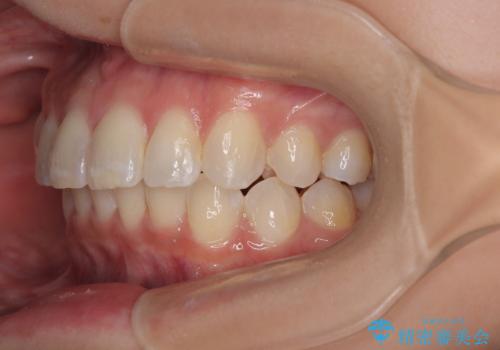

- 上下前歯のデコボコとディープバイトを気にして来院された患者様です。

歯列全体に叢生があり、舌の突出癖が認められたため、突出癖が改善されない場合には口元が突出するリスクが考えられました。

マウスピースでもワイヤーでも対応可能でしたが、煩わしいことは避けたいとのことで、舌のトレーニングをしっかりと行っていただきながら、ワイヤー装置にて矯正治療を行うこととしました。